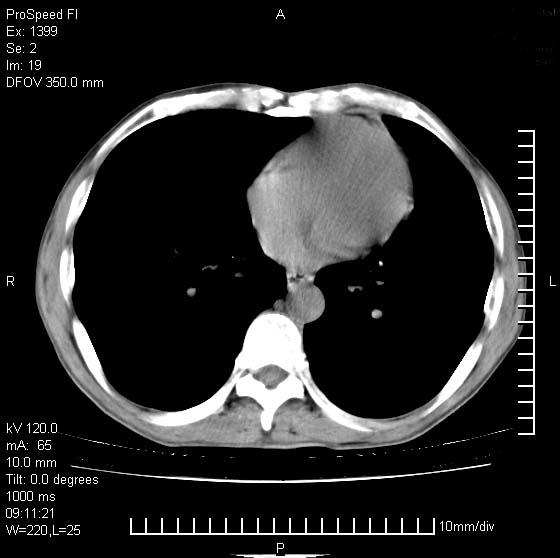

以下是引用卜一在2007-1-19 9:55:00的发言:[br]左肺沿胸膜下巨大肿块影,边缘呈分叶征,纵隔内见肿大淋巴结,右肺内另见一不规则结节影 .考虑:左肺周围性肺癌伴纵隔 右肺内转移.

以下是引用rgsyyf在2007-1-19 11:05:00的发言:[br]左肺上叶见形态不规则巨大软组织肿块影,边缘呈分叶征,纵隔内隆突下见肿大淋巴结,右肺内另见一不规则结节影 .考虑:左肺周围性肺癌伴纵隔即右肺内转移.